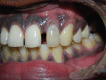

Palatogingival groove is an anatomical malformation that often causes severe periodontal defects. Treatments of such an anomaly present a clinical challenge to the operator. Careful endodontic and periodontal procedures may restore the form and function. In the present case; root canal therapy, apicectomy, and sealing of the groove with Biodentine™ were done. Bone graft was placed followed by platelet-rich fibrin (PRF) membrane. This treatment modality resulted in gain in attachment, reduction in pocket depth, and deposition of bone in the osseous defect. A 24 month follow-up is included.